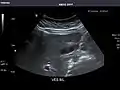

Right kidney

Kidneys: Right and left kidneys measure 11.5 cm and 12 cm in length respectively. No hydronephrosis. Small left lower pole kidney cyst.